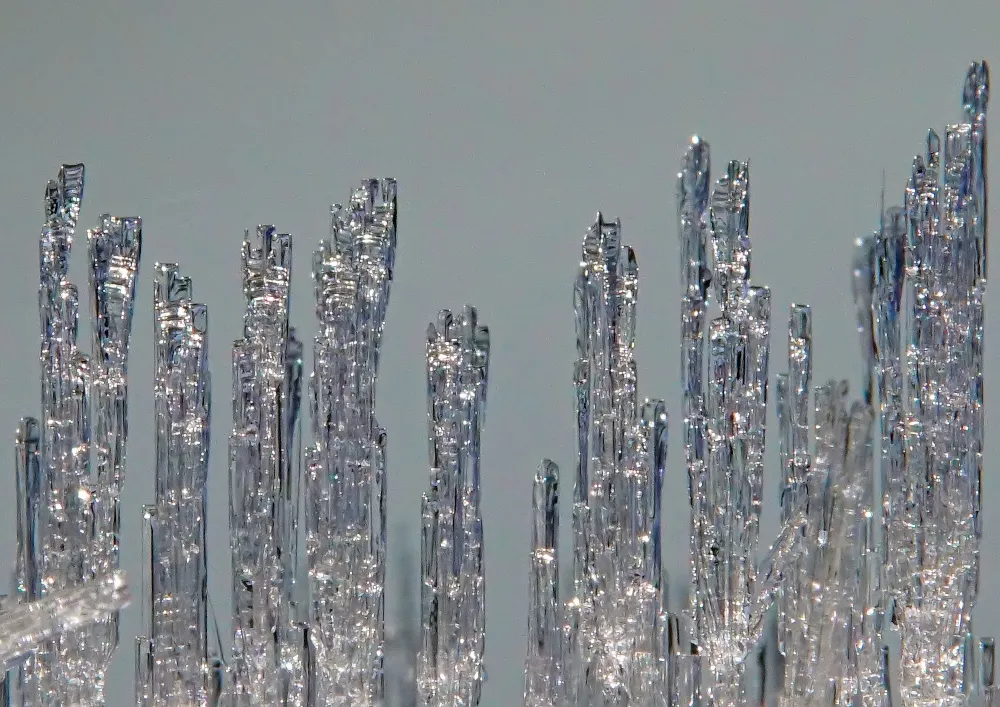

Sometimes ovarian tissue is collected for fertility preservation in adult women too. For example, if cancer treatments must be started immediately, ovarian tissue collection is the only procedure that can be performed rapidly because collection of mature eggs takes several weeks. A piece of ovarian tissue is surgically removed and stored in -180 °C. When the woman has recovered from cancer and wishes for pregnancy, the frozen ovarian tissue can be thawed and transplanted back. There are over 130 babies born after ovarian tissue transplantation in the world. The method is now considered established clinical routine for adult women. However, information on the suitability of this procedure for young girls is limited. There are only two known cases where ovarian tissue collected from girls have led to pregnancies after transplantation. In these cases, the girls were around 10 years old when the ovarian tissue was removed. We do not know if the method works for even younger patients. Importantly, tissue transplantation is not an option for all patients because the tissue may contain cancer cells that could return to the patient. This is the case for blood cancers like leukemias and lymphomas. For these patients, maturation of eggs in the laboratory could be an option in the future. However, no such method exists today.

- What kind of cells is child ovarian tissue made of? Are these cells similar to those in adult ovarian tissue?

- How similar are the immature eggs in child ovaries compared to those in adult ovaries?

- Can immature eggs from child ovaries be matured in the laboratory?